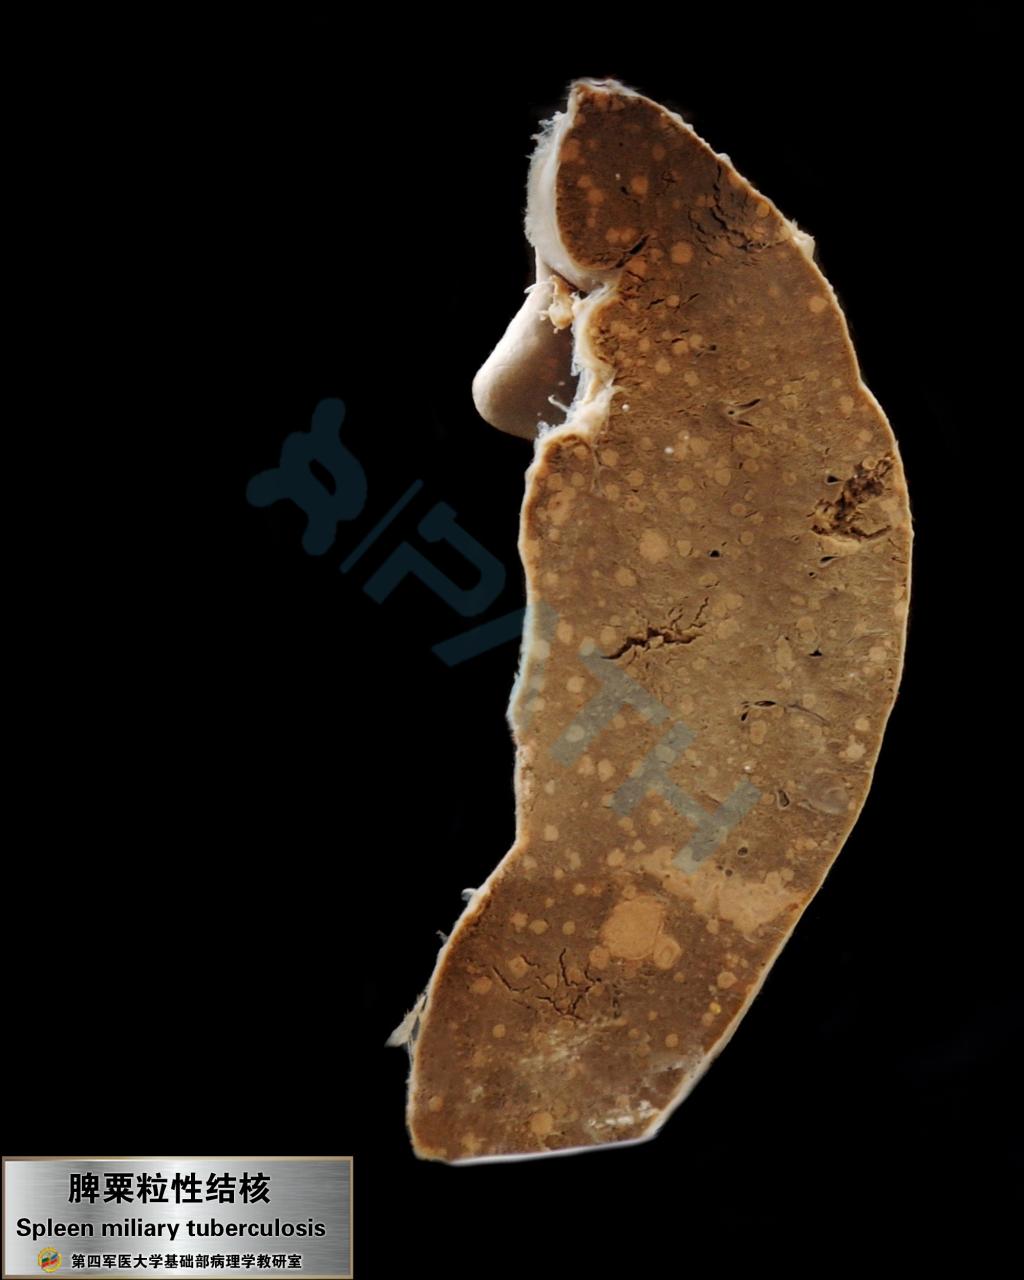

脾结核